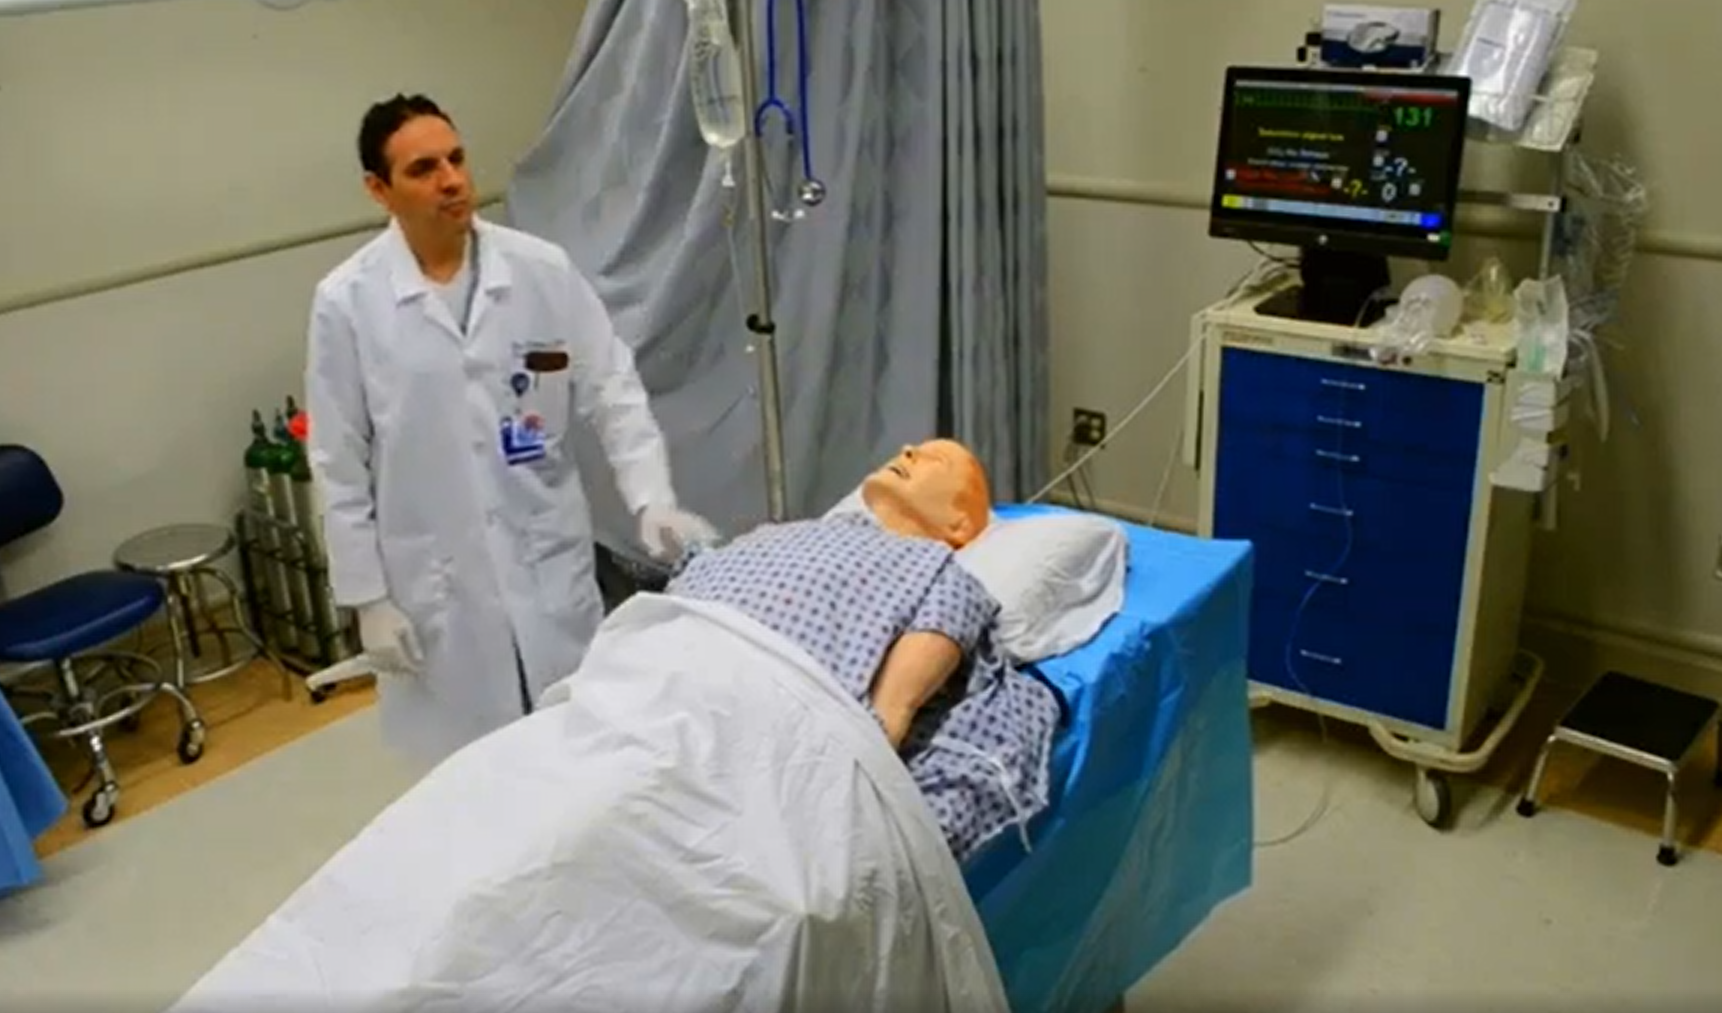

To shorten the duration of interruptions in CPR, protocolized approaches to use ultrasound were developed.15-22 After the introduction of the protocols, the length of CPR interruptions uniformly decreases, although often not to below 10 seconds. With no evidence to support one approach over others, we would like to highlight the EASy-ALS protocol (outlined in Table 1, Figures 1 and 2, and Video 9). The EASy-ALS protocol is the protocol utilized by anesthesiology residents during IHCA.22 This protocol calls for prerequisite training including simulation, which focuses on teamwork, communication, high-quality CPR, and limiting pulse/rhythm checks to fewer than 10 seconds. In our experience, simulation-based training results in consistent shortening of interruptions in CPR during simulated cardiac arrest.23

Supplemental Video 9. Demonstrating EASy-ALS in a simulated setting (click to view)

The responding resident is alerted to an acutely decompensating patient in the SICU or medical or surgical ward by direct call from the primary service or by overhead Code Blue page. On arrival, the resident prepares to serve as a sonographer and complete an EASy-ALS exam. The ultrasound probe is placed in the subcostal window before the pulse/rhythm check without obstructing chest compressions. The code leader, a senior primary care team provider, is responsible for holding and resuming chest compressions. The code leader assigns a nurse to count down 10 seconds during the pulse/rhythm check; this is standard at our institution. After resumption of chest compressions, the resident interprets recorded images and communicates findings to the code leader. The primary phenotypes (Figure 2) to be identified are cardiac standstill (see Video 1), pericardial effusion (Video 2), dilated right ventricle (RV) (Video 5), dilated left ventricle (LV) (Video 6), and underfilled heart (Video 7). The resident can obtain extracardiac views (such as the subcostal IVC View, Video 3), between pulse/rhythm checks.